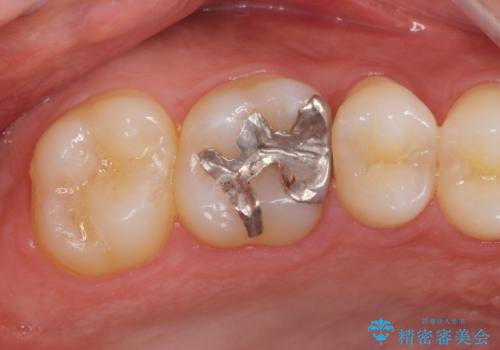

- 銀歯をやりかえたいが他院で抜歯と言われセカンドオピニオンで来院。適合の悪い被せ物が入っており、まずは古い材料、虫歯をとり保存可能か確かめる必要があり、拡大鏡下で全て取り除いたら歯質が歯茎の中まで虫歯がありました。このまま無理やり型取りをして被せ物を作っても不適合な被せ物が入る可能性が高いため歯茎を切り取る手術(ディスタルウェッジ)を行いました。そして再根管治療を行いゴールドの被せ物で治療を行いました。

適合の良い被せ物が入り大変満足して頂けました。